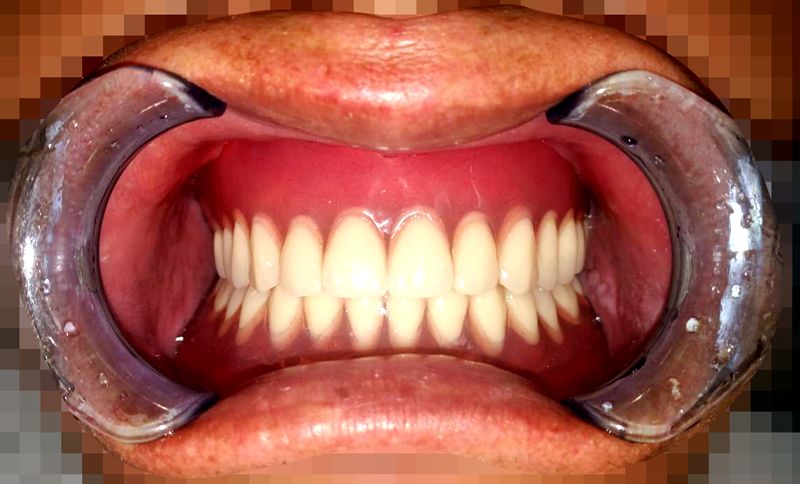

义齿戴入口腔内的情况